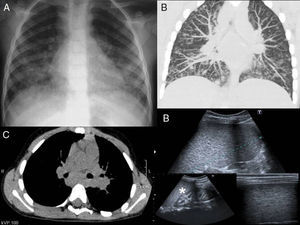

En la exploración física destaca discreta hepatomegalia-esplenomegalia. La radiografía de tórax realizada de urgencias muestra un patrón alveolo-intersticial bilateral con predominio en bases (fig. 1A). El hemograma del ingreso es compatible con proceso infeccioso agudo. La VSG y PCR durante todo el ingreso permanecen normales. La saturación de O2 al ingreso y los gases capilares fueron normales. Los niveles de enzima conversiva de la angiotensina (ECA) se encontraban elevados (236 U/L). Todos los cultivos, incluido el cepillado bronquial, fueron negativos, así como el resto de estudios microbiológicos. En los controles radiográficos posteriores se observa la aparición de adenopatías mediastínicas e hiliares, con mejoría del patrón descrito. Se realiza ecografía abdominal, en la que se identifican esplenomegalia y múltiples adenopatías periesplénicas y retroperitoneales, así como en fosas iliacas, y una importante nefrocalcinosis (fig. 1D). Se realiza tomografía computarizada (TC) toracoabdominal que confirma los hallazgos descritos, apreciándose en el parénquima pulmonar un patrón pulmonar alveolo-intersticial difuso y bilateral, con presencia de nódulos de aspecto acinar, engrosamiento de septos interlobulillares y áreas de vidrio deslustrado; adenopatías hiliares y mediastínicas (fig. 1B-C).

A. Rx de tórax, ensanchamiento de las bandas paratraqueales y aumento de tamaño hiliar secundario a la presencia de adenopatías. Aumentos de densidad mal definidos basales bilaterales, con tendencia a la confluencia, asociado a pequeñas imágenes nodulares. B. TC de tórax, opacidades nodulares en vidrio deslustrado y nódulos bien definidos distribuidos difusamente. Engrosamiento de septos interlobulillares. C. TC de tórax, adenopatías hiliares y subcarinales. D. Ecografía abdominal, esplenomegalia con presencia de multitud de lesiones focales hipoecogénicas de pequeño tamaño debidas a la presencia de granulomas. Aumento de ecogenicidad de las pirámides renales, ocasionado por depósitos de calcio y nefrocalcinosis. (asterisco).